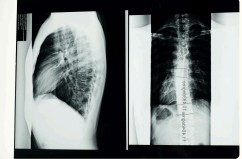

Any time we do have changes like the ones shown in the image below, it results in altered biomechanics. Your joints and muscles will have to move differently and adapt. The potential for abnormal/accelerated degeneration or pressure on the nervous system is there, but usually it depends on the severity of the change or abnormality.